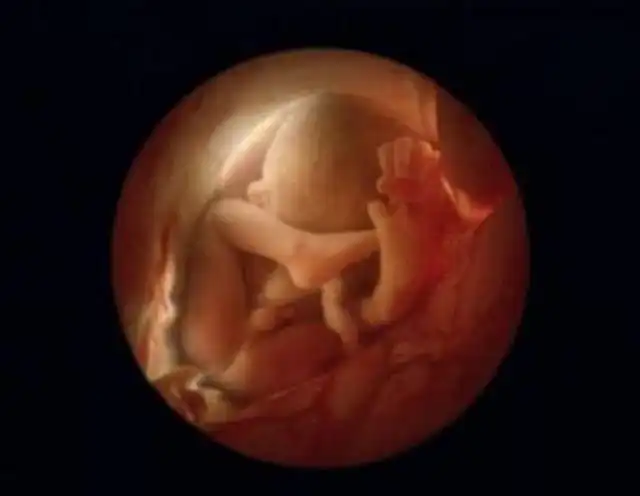

16 недель. Любознательный малыш уже использует свои руки для изучения окрестностей.

Скелет в основном состоит из гибкого стержня и сети кровеносных сосудов, видимой сквозь тонкую кожу.